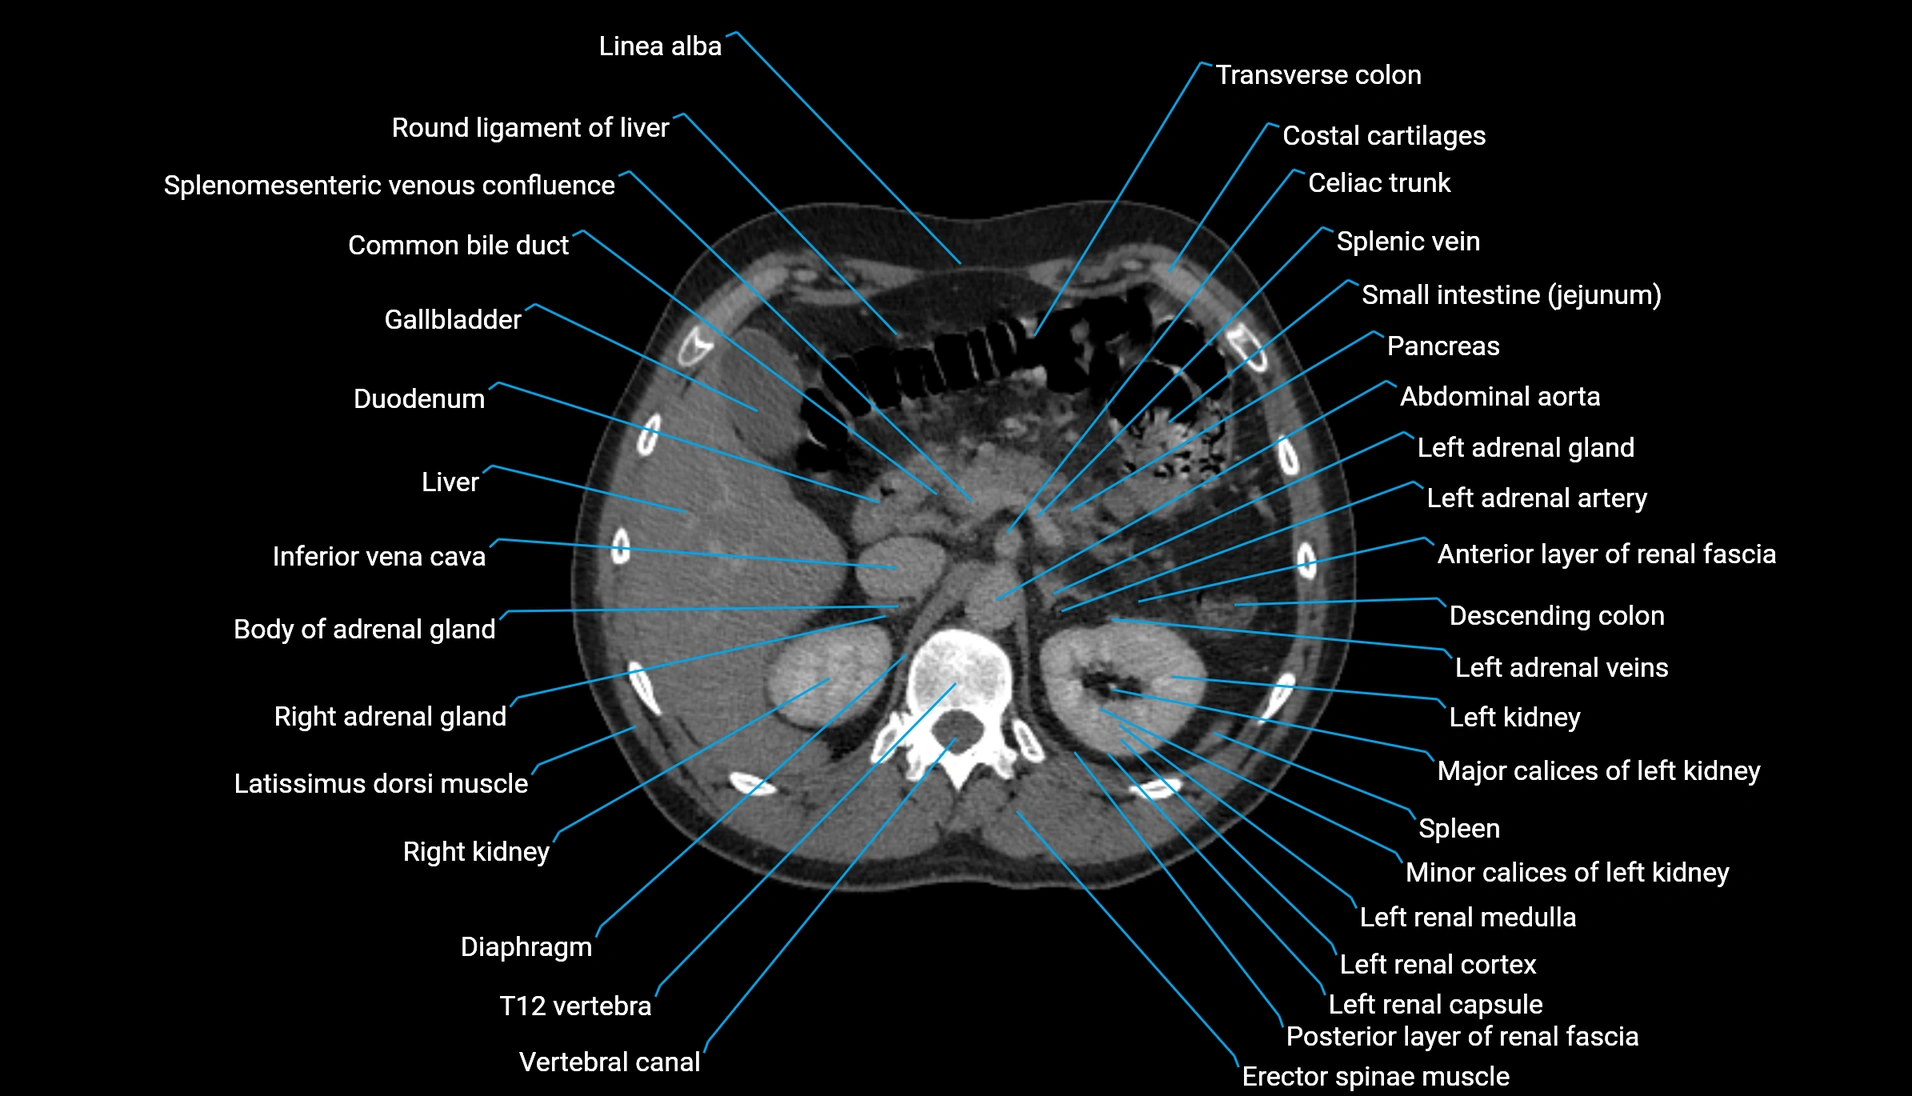

CT Appearance

Non-contrast CT:

-

Demonstrates cortical bone of acetabular rim in excellent detail

Detects fractures, dysplasia, retroversion, or bony overcoverage (pincer impingement)

3D reconstructions used in preoperative hip surgery planning

CT VRT 3D image

CT image